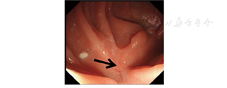

例1 患者男,55岁,因"进食后呛咳5个月余"于2018年4月10日入院。2017年9月患者因发现食管癌行食管癌根治术。术后偶有进食后呛咳。患者于2017年10月出现胸闷气喘,伴血氧饱和度下降。于当地医院行上消化道造影检查提示食管气管瘘。长期空肠营养管鼻饲饮食,间断抗感染治疗,其间患者因长期鼻饲饮食致能量严重摄入不足,体质量下降10 kg。2018年3月患者于江苏省人民医院行胃镜检查见吻合口局部有一直径约为3 mm的瘘道,瘘口周围黏膜光滑(图2A);上消化道造影检查提示食管气管瘘(图2B)。于2018年4月13日行内镜下OverStitch缝合术闭合瘘口,手术过程顺利,术中使用1根缝合线,缝合6针,总手术时间约为50 min。术后第2天予流质饮食,症状改善,于2018年4月16日出院。术后3个月复查胃镜和上消化道造影均提示瘘口已闭合(图3),患者无胸闷、气喘,无进食后呛咳,体质量增加约8 kg。